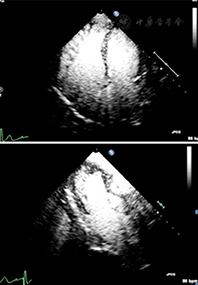

距离探头最近区域和聚焦区域的造影剂微泡破裂严重。如果是实时观察左室影像,由于气泡的破坏可观察到无造影剂增强或心尖区涡流。近场涡流成因是多因素的,主要成因是MI设置过高或注射造影剂剂量不足。通过及时注入新制备的造影剂进入心室腔补充或代替被破坏掉的造影剂的方法可以使涡流伪像消失;如果血流缓慢,新注入的造影剂未能及时充分替代被破坏的造影剂,则在流速最低的区域或高MI时,还会有涡流伪像。生理原因引起的心尖部血流速度超低(严重左心功能不全或心尖部大的室壁瘤)也是涡流伪像的常见原因(图1)。